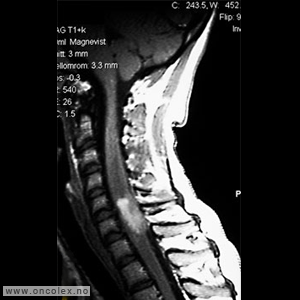

Bildediagnostiske undersøkelser

MR er det viktigste diagnostiske hjelpemiddel for å påvise svulst i ryggmargen, ryggmargsnervene og ryggmargshinnene. CT kan også brukes, men har klare begrensninger når det gjelder fremstilling av svulstene. Blant annet kan svulster som ikke tar opp kontrast bli oversett. CT og skjelettrøntgen kan imidlertid være nyttig for å kartlegge grad av skjelettødeleggelse og eventuell instabilitet i ryggsøylen.